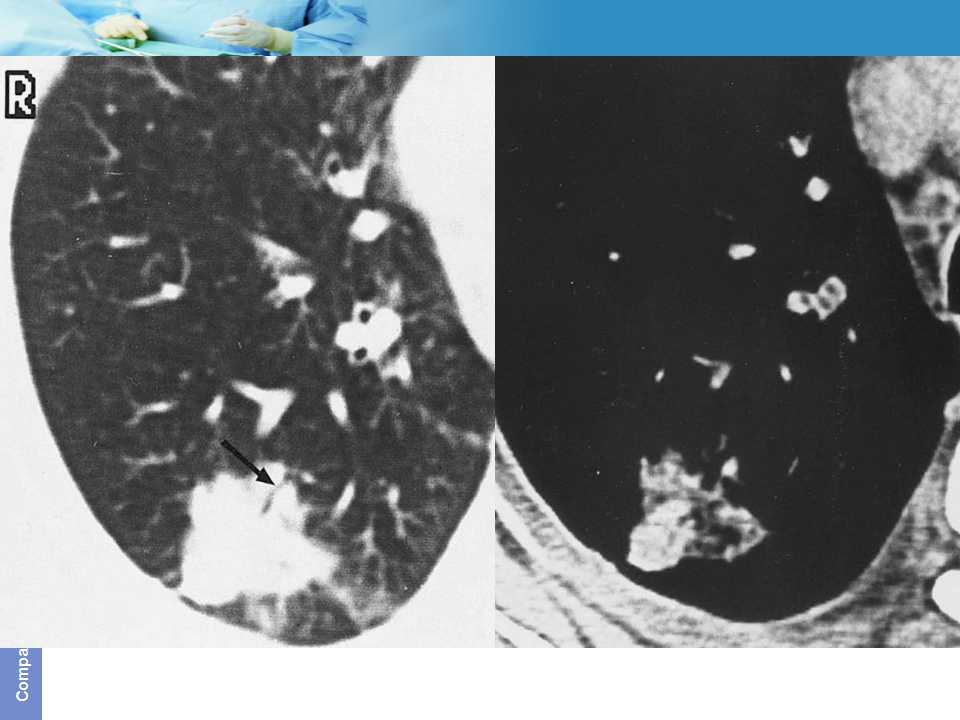

肺癌影像诊断